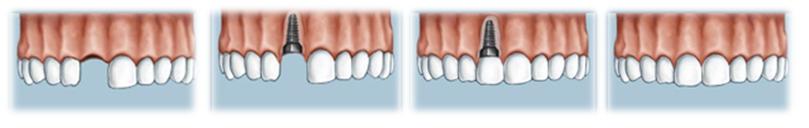

După 10 zile de la intervenţie, se îndepărtează firele de sutură care au ajutat la vindecarea gingiei. Implantul de titan nu va fi aşadar vizibil timp de aproximativ 3-4 luni, interval necesar pentru integrarea lui în os şi vindecare.

După perioada de vindecare, peste implant se va monta un “şurub de vindecare” pentru a face loc în gingie coroanei de ceramică. Aceasta se produce relativ repede, în câteva zile (10-14 zile).

În acesta etapă, peste implant se va pune “bontul” care va susţine coroana dentară din ceramică. Acestui bont i se va lua o amprentă care va servi la realizarea coroanei dentare în laborator.

Coroana din ceramica va fi definitiv montata peste implant fie prin cimentare fie prin insurubare.